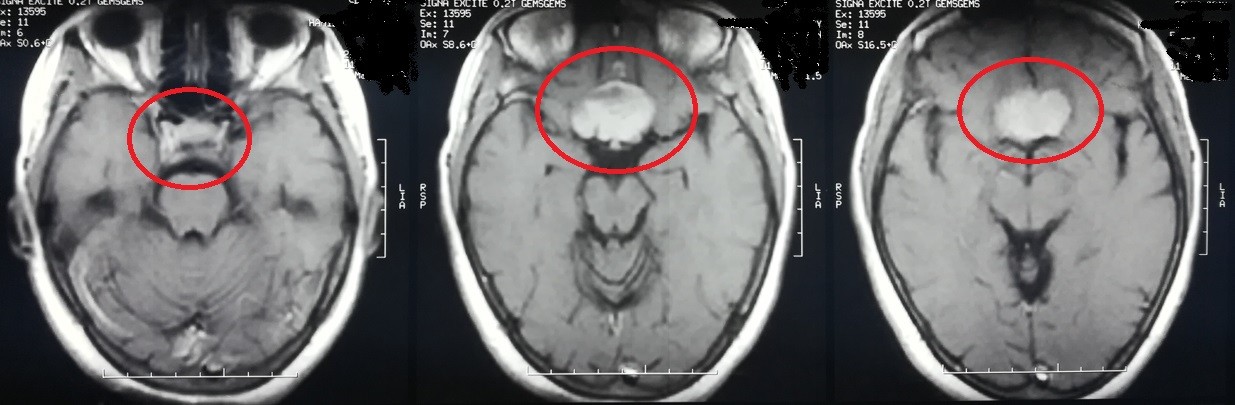

sphenoidal meningioma